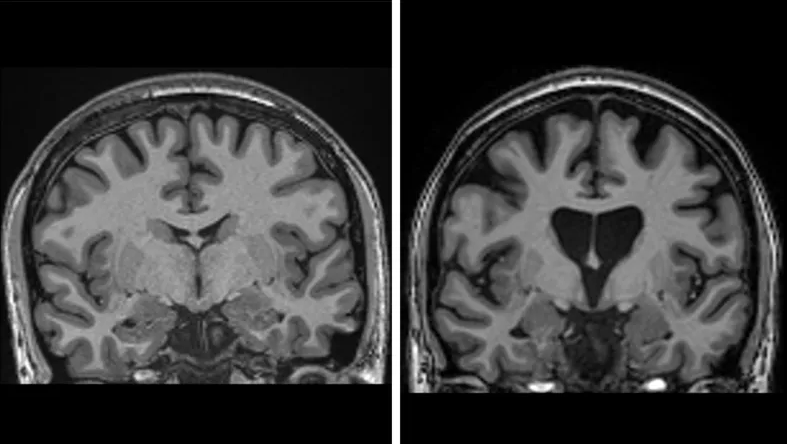

Ліворуч зображено здоровий організм, праворуч – втрату мозкової речовини через гибель нейронів при хворобі Гантінгтона